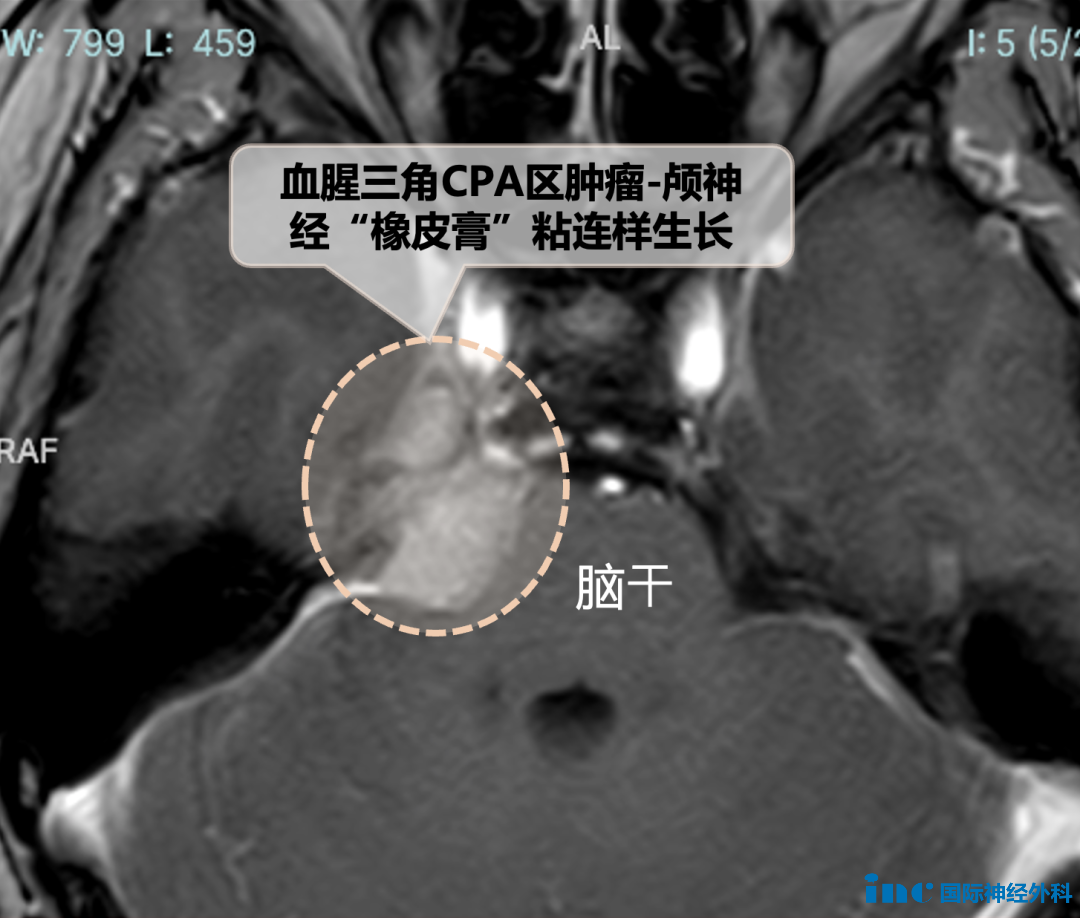

41岁周女士,体检发现的桥小脑角(CPA)区脑膜瘤。小小肿瘤却长得刁钻,和脑神经中最细的神经滑车神经、三叉神经间呈“橡皮膏关系”——黏得严严实实!此外,生命中枢的桥脑和中脑也受到压迫。不同于多数患者等到剧烈头痛、面瘫偏瘫才发现脑瘤,这份体检报告反而成了不幸中的幸运,让周女士在神经功能尚好时抓住了黄金窗口期,寻求巴教授示范手术,得以早早切除肿瘤。点击阅读:天坛医院手术纪实 | 偶然发现、无症状,被体检报告“揭发”的脑瘤,切吗?